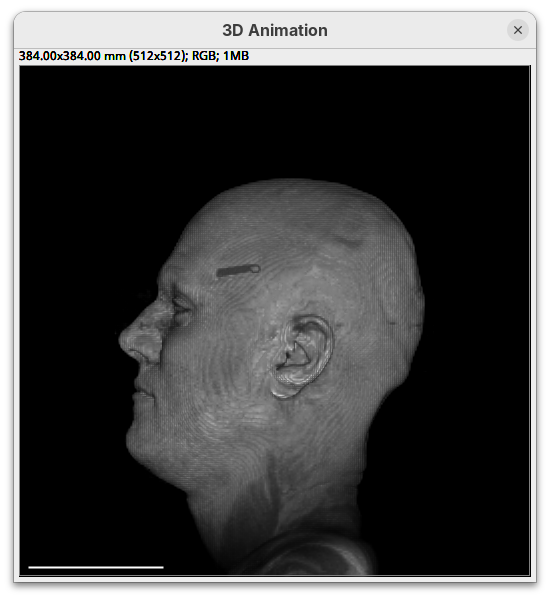

Note that this improves the visualization as the head’s surface becomes better visible.

- Now set the alpha

maxto250.

The surface will become even more solid because we are defining that pixels that have a value above 250 will be fully opaque.

- To compare, set alpha

maxto5000.

You will notice that the sample will become more transparent. Even the brain inside the skull will be visible.

- Set alpha

maxback to500.

Generally, setting the intensity and alpha to the same values is a good starting point for optimizing the rendering.